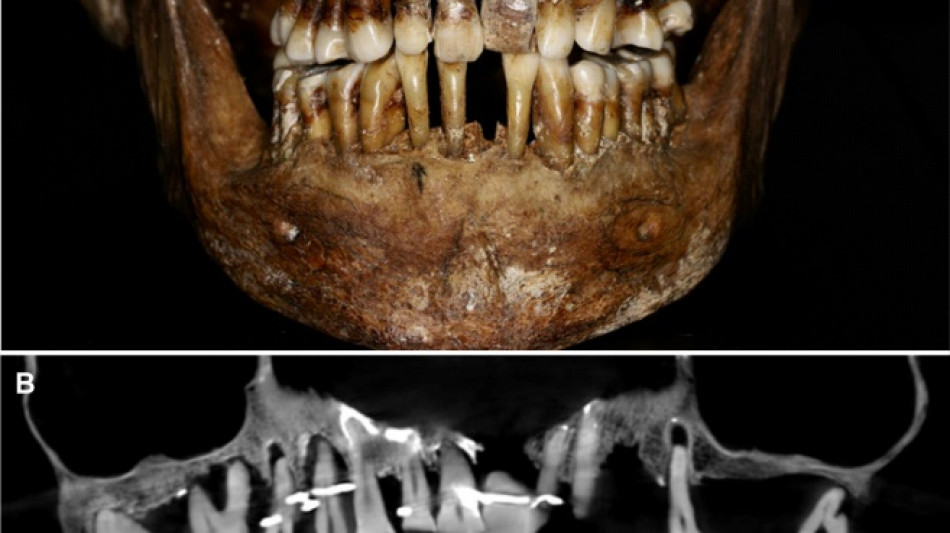

French aristocrat's golden dental secret revealed 400 years on / Photo: © INRAP/Rozenn Colleter/AFP/File

Thirty-five years later, a team of archaeologists and dentists have identified that d'Alegre suffered from periodontal disease that was loosening her teeth, according to a study published in the Journal of Archaeological Science: Reports this week.

A "Cone Beam" scan, which uses X-rays to build three-dimensional images, showed that gold wire had been used to hold together and tighten several of her teeth.

She also had an artificial tooth made of ivory from an elephant -- not hippopotamus, which was popular at the time.